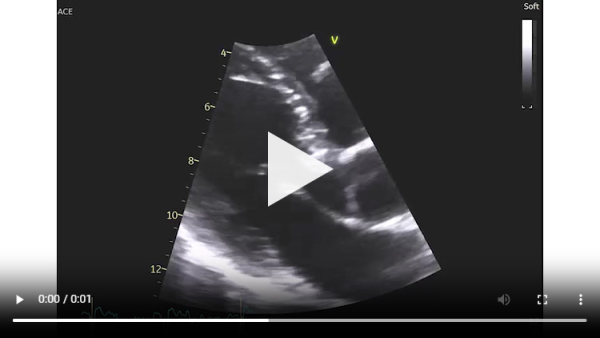

Vidéo 2 : échocardiographie 2D en incidence apicale des 4 cavités